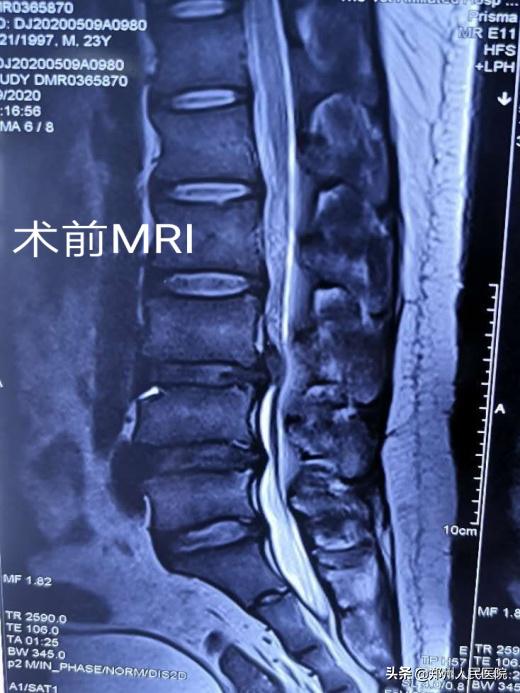

小葛立即去了省内的几家大医院看病,经过各项检查后,他被确诊存在“腰3/4椎间盘突出并髓核脱出,伴有椎管狭窄”。最让小葛纠结的是:每个医院给出的治疗方式不同,各种各样的治疗方式让小葛难以抉择。有的说可以保守治疗,有的说可以做微创手术,有的说必须进行开放手术效果才好。

田明波主任在听到小葛的情况后立即召开了全科室的病例讨论,针对患者的腰椎间盘椎管狭窄病情及患者年龄的特殊性进行反复论证,最终选择使用国内前沿的“单侧双通道UBE脊柱内镜技术”为小葛行手术治疗。

经过充分准备,对小葛实施的“单侧双通道UBE脊柱内镜术”如期举行。手术进行的十分顺利,经过一个半小时,手术成功。